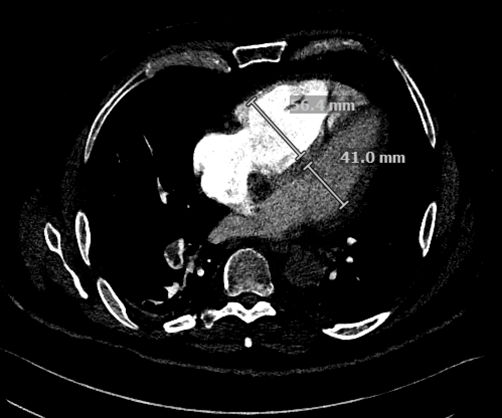

Figure˜2 shows two anonymized CTPA images from patients with PE. Panel A shows the upper chest where the main pulmonary artery splits. The grey area inside the right pulmonary artery (left side of image) is a blood clot blocking flow. The vessel should appear uniformly white from the contrast dye. Panel B shows the heart chambers. The right ventricle measures 56.4 mm compared to 41.0 mm for the left ventricle. Normally the left ventricle is larger. The enlarged right ventricle indicates the heart is working harder to pump blood through the blocked vessels. Together, Panel A reveals a clot’s location while Panel B reveals the resulting heart strain.

The figure shows two CTPA images from patients with PE. Each image shows a horizontal slice through the chest, as if looking upward from the fee. Panel A shows the upper chest where the main pulmonary artery splits into left and right branches. A grey area appears inside the right pulmonary artery (left side of image) where the vessel should be uniformly bright white from contrast dye. This grey area is the blood clot blocking blood flow. Panel B shows a lower slice through the heart chambers. The right ventricle measures 56.4 mm compared to 41.0 mm for the left ventricle, producing an RV/LV ratio of 1.37. Normally the left ventricle is larger (RV/LV < 1). The enlarged right ventricle indicates the heart is straining to pump blood through the blocked lung vessels. Together, the images illustrate both the direct evidence of PE (the clot itself in Panel A) and its cardiac consequence (right heart strain in Panel B). De-identified CT images courtesy of the hospital system studied.